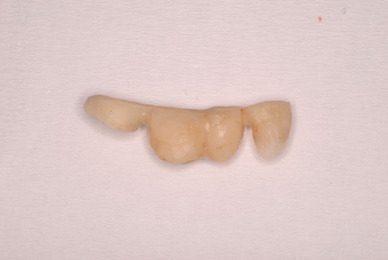

お口の中から差し歯、入れ歯、詰め物を追放しましょう!

二度とお口の中へ変なものを入れなくても済むように